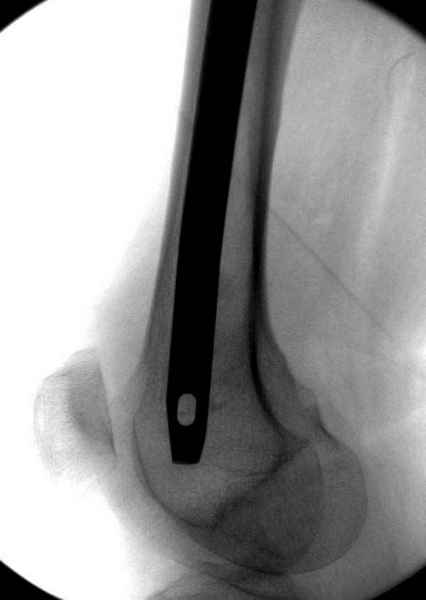

Правильно, ситуация изменилась, как говорят у нас теперь "different animal", надо решать проблему подвертельного перелома. При наличии различных вариантов фиксаторов, включая Страйкер Гамма 3, мы выбрали DePuy Antegrade Trachanteric Nail из-за многовариантности проксимальной фиксации и двойного изгиба. Вводится через вертел под 8 градусным углом, и есть достаточный передний диафизарный изгиб, предупреждающий пенетрацию дистального переднего кортекса.